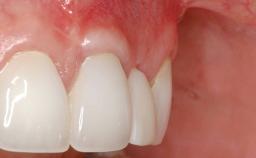

Connective-Tissue Graft to Increase the Width of the Keratinized Mucosa Around an Osseointegrated Implant

Adequate peri-implant soft-tissue thickness is essential not only for esthetic but also for functional reasons. In this case, Vincenzo Iorio Siciliano demonstrates how he achieved increased height and thickness of posterior peri-implant soft tissues to obtain a stable mucosal seal and a width of keratinized tissue favorable to toothbrushing.

The patient, a healthy 38-year-old woman, was referred for increasing the width of the keratinized tissues at the buccal aspect of dental implant 46. The site exhibited a premature-closure screw exposure caused by trauma during chewing, with inadequate keratinized tissue.